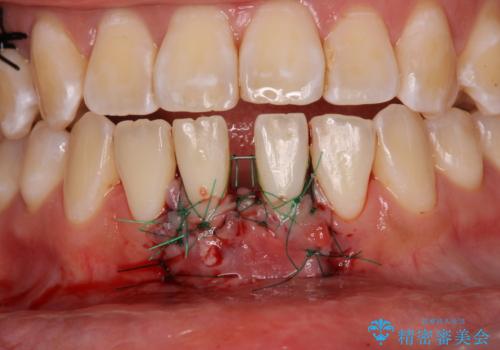

舌のトレーニングをしっかりと行っていくことを前提に、歯肉移植による根面被覆と、部分矯正によるすきっ歯の改善を行うこととしました。

歯肉移植と矯正治療後には非常に満足のいく仕上がりとなりましたが、舌の突出癖は残存しており、今後歯肉退縮とすきっ歯になるリスクを抱えた状態での治療終了となりました。

- 外科手術のため、術後に痛みや腫れ、違和感を伴います

- 歯周組織再生治療は患者様の状態によって術後の経過が異なります(見た目が改善しない場合もあります)